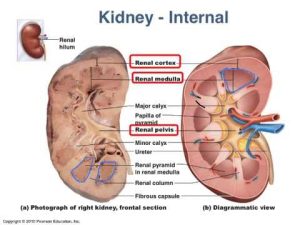

Kidney stones are hard masses that can grow from crystals forming within the kidneys. Doctors call kidney stones “renal calculi,” and the condition of having such stones “nephrolithiasis.”Most kidney stones are made of calcium oxalate. People with a history of kidney stone formation should talk with their doctor to learn what type of stones they have—approximately one stone in three is made of something other than calcium oxalate and one in five contains little if any calcium in any form. Calcium oxalate stone formation is rare in primitive societies, suggesting that this condition is preventable.1People who have formed a calcium oxalate stone are at high risk of forming another kidney stone.